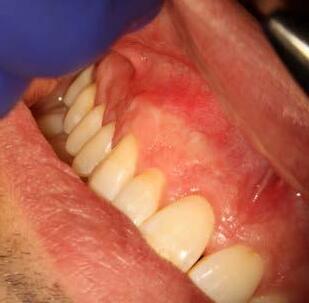

This is not a “Terminal Dentition”. It is interesting to see the increase in patients being advised that Periodontitis is not treatable or that treatment is somehow expensive and ongoing maintenance is difficult/unachievable. These patients are usually advised to receive implant treatment as an alternative.

This patient first presented in 2016 at the age of 33 years. He was a former smoker (quit two years prior to the initial presentation). He presented with generalised deep pocketing and advanced loss of attachment.

Radiographic assessment showed generalised moderate to advanced bone loss with most teeth showing bone loss to more than 50% of the root length. Given the established loss of attachment in relation to his relatively young age, this patient was diagnosed with generalised aggressive periodontitis. According to the 2017 Classification of Periodontal Disease, he would be Stage III, Grade C Periodontitis.

The patient was managed with non-surgical periodontal debridement. Two months later, he presented with an encouraging reduction in periodontal probing depth (PPD). There were 85% sites with PPD 1-3mm, 15% sites with PPD 4-5mm and no sites with residual PPD > 6mm. The patient showed excellent plaque control measures and his bleeding on probing score was 1%. The patient has been placed on a six-monthly periodontal maintenance program with the periodontist. He also sees his general dentist once annually. The OPG images dated 2016 and

2023 show stable bone levels with no evidence of further bone loss.

The patient had orthodontic treatment between 2018-2020 to address the flaring and spacing of his teeth, which was a cosmetic concern to him (orthodontic treatment done by Dr Frank Furfaro). Long-term evidence shows that we, as dental clinicians, are not accurate at determining the prognosis of periodontally compromised teeth (McGuire 1996). We may also be hasty at labelling such teeth as “hopeless”. The threshold at which we

decide to extract teeth due to periodontal disease may be too low (Splieth 2002). There is no evidence on the other hand that dental implants have longer survival or less complications or better cost compared to periodontally treated teeth.